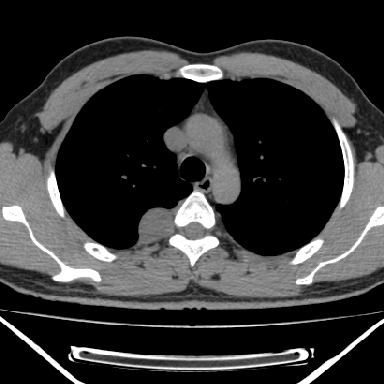

m 30 右胸痛10年

右上后纵隔脊柱旁类圆形肿块,边界光整,与胸腔呈钝角,首先考虑来源于肺外,神经源性肿瘤(神经鞘瘤可能大,神经鞘瘤)

m,30岁,右胸痛10年。

右上后纵隔旁软组织肿块影,与肺界面光滑,与胸壁呈钝角相交,提示肺外病变。位于肋骨下缘,边缘清楚,呈三角样指向与右侧椎间孔,但并示进入椎间孔;与对侧神经根对比,属同一走行方向。

考虑后纵膈良性肿瘤,神经源性肿瘤可能大。

鉴别:胸膜来源肿瘤。影像表现虽有肺外征象,但无胸水等相应佐证;再者,病史前10年,超长,与胸膜肿瘤不太吻合。

建议:再次查体,问清疼痛部位,如为1~2个肋间痛则神经源性肿瘤可能大,如疼痛较弥散,不按肋间分布,则可能为后纵膈其它来源肿瘤。

右上后纵隔脊柱旁类圆形肿块,边界光整,与胸腔呈钝角,首先考虑来源于纵膈,神经源性肿瘤可能大。

右上后纵隔脊柱旁见长椭圆形肿块,边界光整,与胸壁呈钝角。周围骨质未见异常。

考虑、1、后纵隔神经源性肿瘤;

2、不除外单发胸膜间皮瘤。